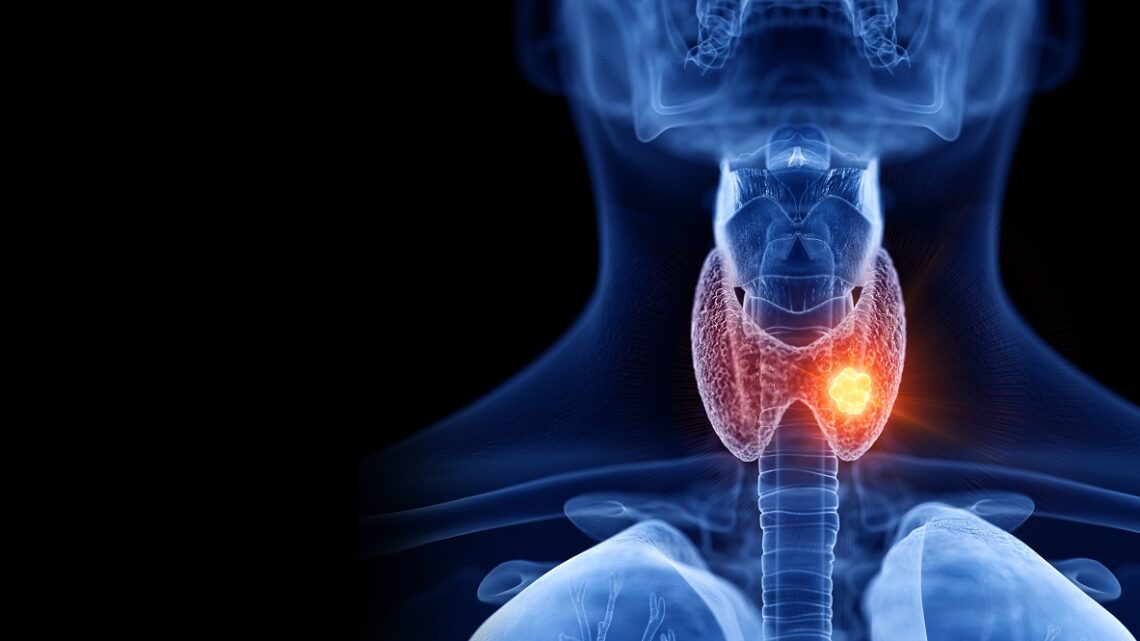

PROCEDIMIENTO MÍNIMAMENTE INVASIVO PARA NÓDULOS TIROIDEOS

24 noviembre, 2022Un “nódulo tiroideo” es el crecimiento de una parte de la glándula tiroides; una lesión focal que difiere de la estructura del tejido tiroideo.

Se identifica por inspección o palpación de cuello y generalmente constituye un hallazgo incidental. Siempre se requiere de un protocolo de estudios paraclínicos ya que la mayoría de los nódulos tiroideos son asintomáticos. Para la resección de los nódulos tiroideos, anteriormente, la opción inicial era la cirugía, la cual es un proceso invasivo y de lenta recuperación para el paciente. Pero ahora, expertos del Hospital Houston Methodist están implementando una nueva opción en el campo de la tiroides.

Con el lanzamiento de su nuevo programa de ablación por radiofrecuencia (RFA por sus siglas en inglés), dirigido por el doctor Helmi Khadra, cirujano oncólogo, ofrecen este innovador tratamiento mínimamente invasivo para los nódulos tiroideos.

La RFA usa guía por ultrasonido y ondas de radio de alta intensidad para reducir (o “cocinar”) tumores, nódulos y otros crecimientos. Aunque la tecnología se ha utilizado clínicamente durante décadas en otros campos, recientemente evolucionó para que sea segura de usar en el cuello, donde las funciones complejas y críticas están fuertemente concentradas. En 2018, la FDA aprobó la RFA para su uso en nódulos tiroideos compresivos benignos. Desde entonces, las indicaciones se han ampliado para incluir neoplasias malignas de menos de 1 cm y tumores metastásicos de los ganglios linfáticos del cuello.